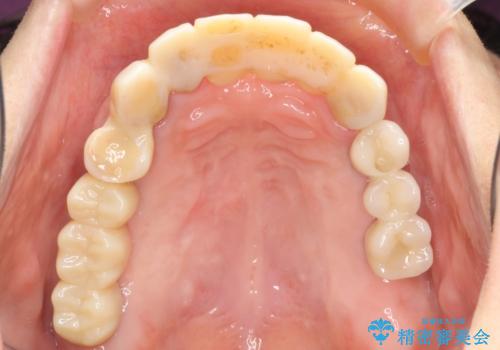

歯周病 全顎治療

- 前歯の見た目、入れ歯による噛めないことの改善を求めて来院されました。

検査により全顎的な歯周病治療、欠損のインプラント補綴、根管治療が必要な状態であることをお伝えし、治療を計画します。

全体的な歯周病が認められる場合、歯を失った一部のみの治療となることはほぼありません。

失ってしまった機能を回復し、今後歯を失わないよう残せる歯に歯周病治療を行い、安定した咬合を確立することで長期的に問題なく噛めるような口腔内環境を達成できるようになると考えます。